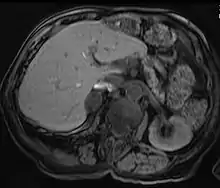

| Adrenal adenoma in a patient with Conn syndrome | |